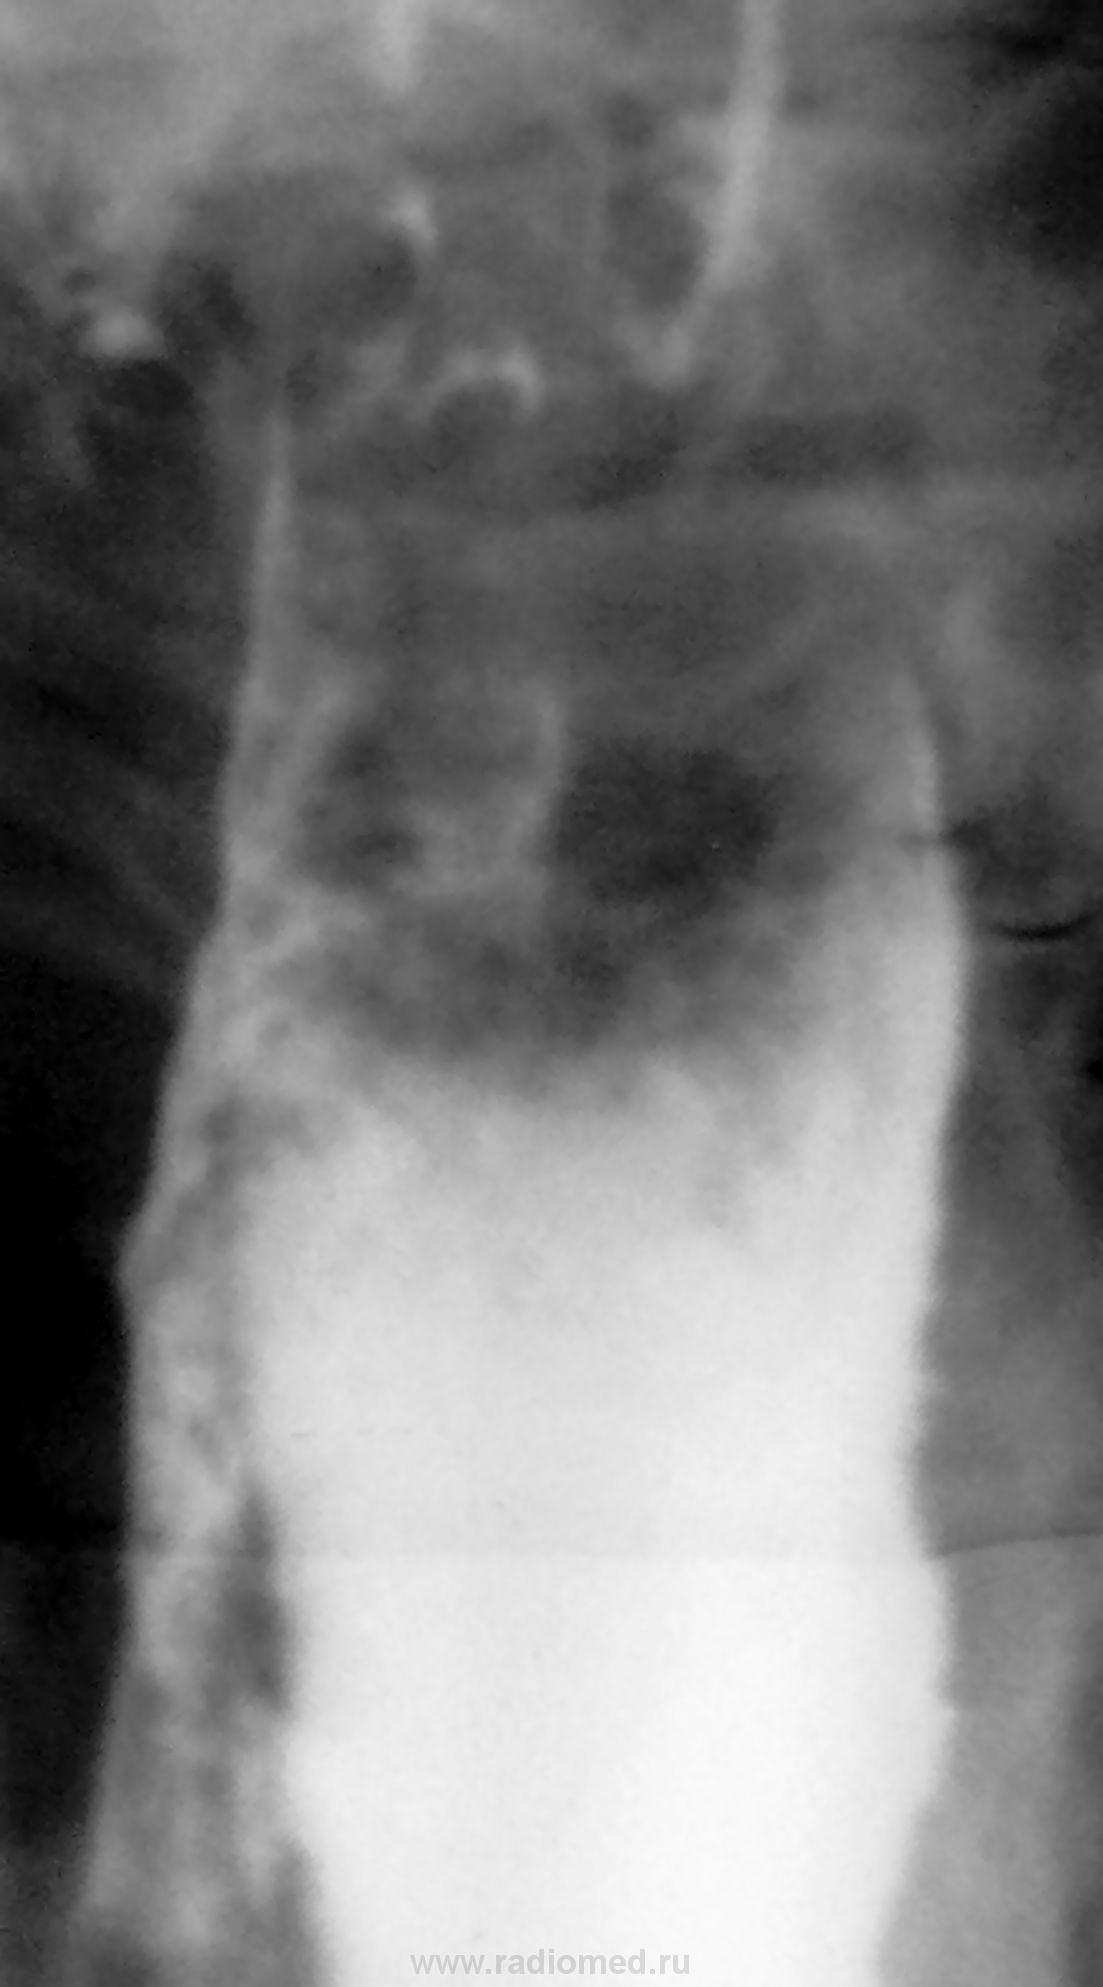

Пациент оказался на редкость скрытным, выудить ничего особого не удалось (может ранее какую агрессивную гадость пил?). Жалобы на "рвоту" сразу после принятия пищи. На 1-м глотке увидел аспирацию в трахео-бронхиальное дерево, кашель. Исследование затруднено. Судя по виду пищевода - свищ где-то в бронх. сегменте. А может что в глотке не так? Больного забрали в др. больницу в хирургию, дальнейшая судьба не известна.

Игорь Иванович, судя по тому, что контрастом обмазаны трахея и оба главных бронха, либо свищ выше - что сомнительно, либо здесь нарушение разделительной функции надгортанника, вероятно за счет сдавления возвратного нерва увеличеными л/узлами. Второй вариант мне представляется более логичным.

Остается только гадать. Может и надгортанник виноват, но и пищевод явно рсширен, и заканчивается на одном уровне (снимков было больше, но картина одинаковая). Да и рассмотреть не было возможности из-за приступов кашля при малейшем глотке.

Изменения в пищеводе сомнений не вызывают. Мой комментарий относился исключительно к наличию свища.

Свищ сомнителен. А получившаяся бронхография связана с нарушением акта глотания.